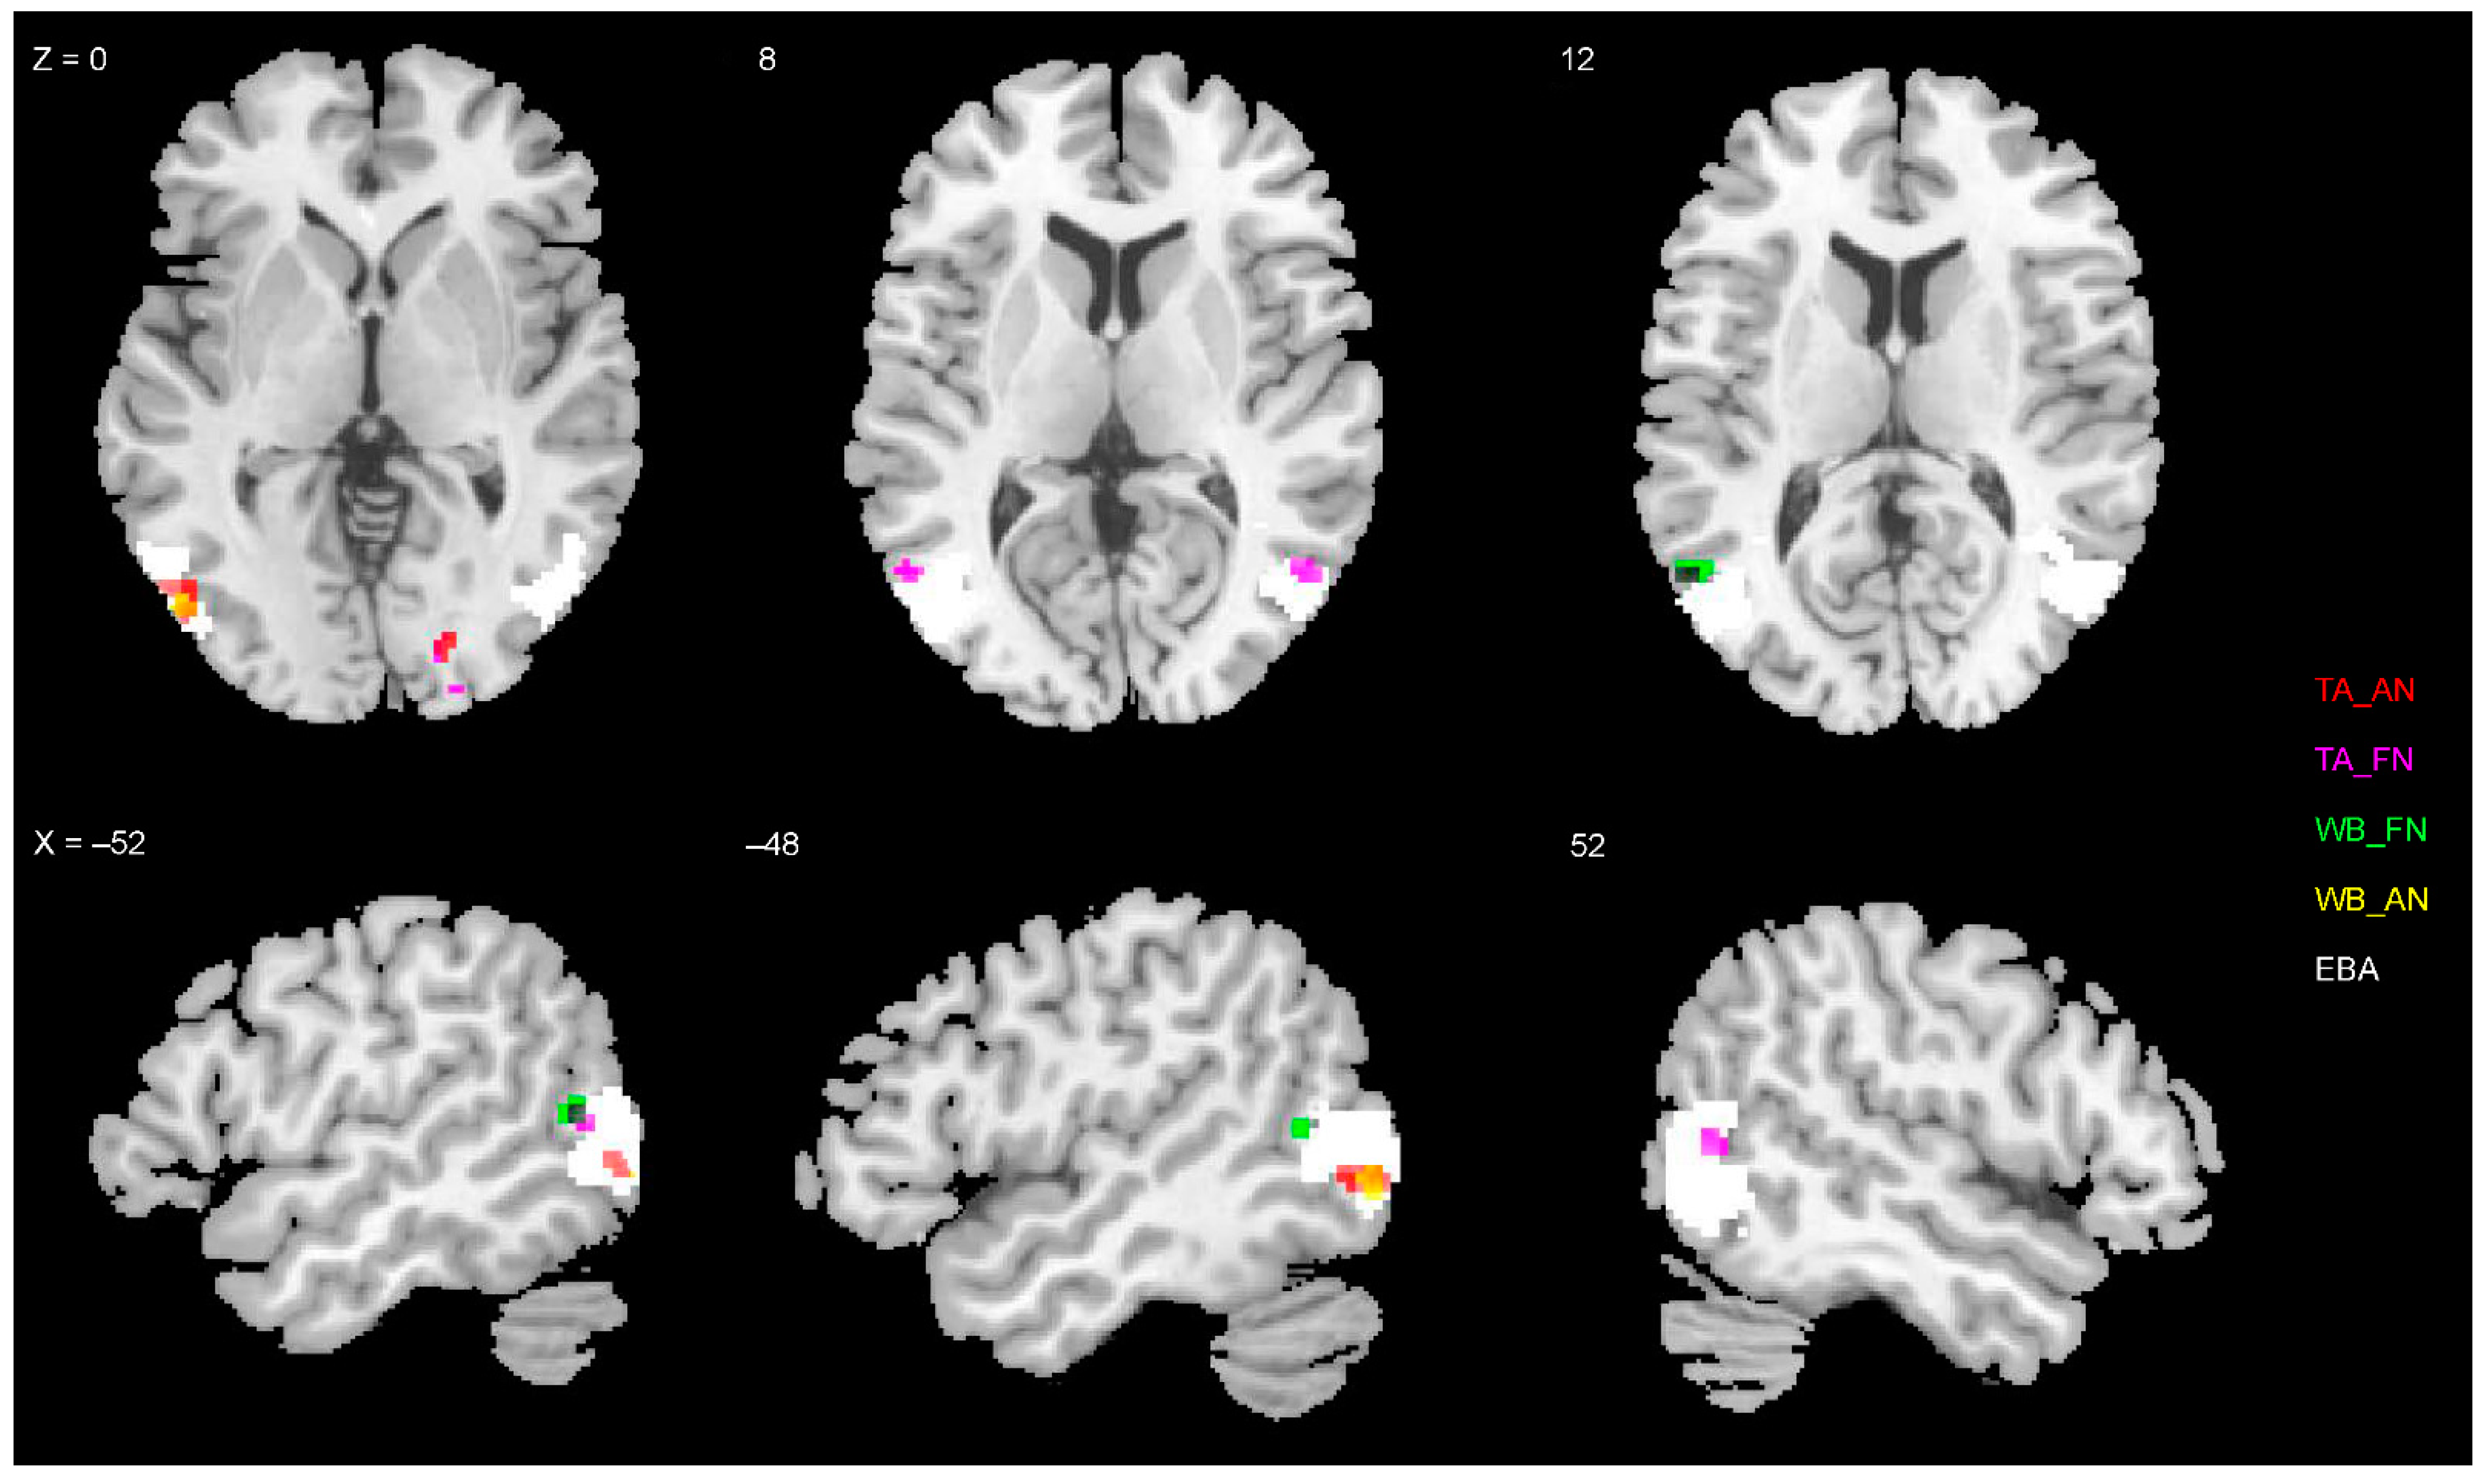

3.4. Representations of EBA and FBA

3.5. Statistical Inference of RSA